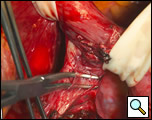

The surgical approach is a left posterolateral thoracotomy, entering the chest over the bed of the unresected 7th or 8th rib. On entering the thoracic cavity, the pulmonary ligament is divided and the lung is packed out of the way superiorly. The epiphrenic diverticulum is often found at the level of the inferior pulmonary vein. The pleura over the esophagus is divided allowing the esophagus to be gently mobilized. Penrose drains are used to encircle the esophagus superior and inferior to the diverticulum to facilitate the dissection (Figure 3). The diverticulum often arises to the right side necessitating rotation of the esophagus to clearly visualize the neck of the diverticulum. The diverticulum and its base are carefully dissected from the adjacent esophagus (Figure 4). Both vagus nerves are clearly identified and preserved during this maneuver. Once the diverticulum base is defined, a 40 Fr bougie is introduced across the gastroesophageal junction. This is performed under direct vision with the surgeon closely monitoring the safe passage of the bougie.